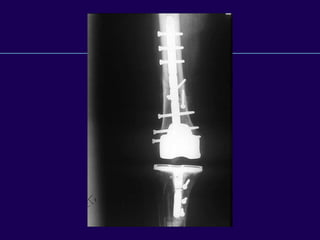

Complications in Total

Knee Arthroplasty

Periprosthetic Fractures

Infected Total Knee

Arthroplasty

Supracondylar

Fractures of the

Femur

After Total Knee

Supracondylar Fractures

After TKR

l Notching of the femoral cortex

l Osteoporosis

l Prolonged steroid use

l Preexisting neurologic

disorders